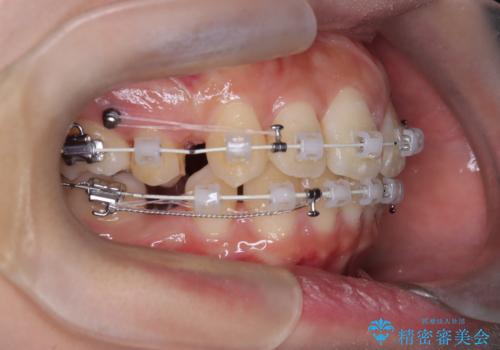

- 矯正装置

- 審美ワイヤー

- 口元が出ていること(突出感)を気にされ、これを下げたいという主訴でご来院されました。精密な検査の結果、前歯を大きく後退させ、口元を改善するためには、スペースの確保が不可欠と診断しました。そこで、上下左右の第一小臼歯(4番目の歯)を計4本抜歯し、そのスペースを利用して前歯全体を奥へ移動させる抜歯矯正の治療計画を立案。確実な歯の移動を実現するため、ワイヤー矯正装置を使用しました。

今回の矯正治療では、口元の突出感を解消するためのスペースを確保するため、計画通り上下左右4本の小臼歯を抜歯しました。装置には、確実な歯の移動と細やかな調整が可能なワイヤー矯正を採用。抜歯によってできたスペースを最大限に利用し、前歯を奥へ、そして垂直的に慎重に移動させました。